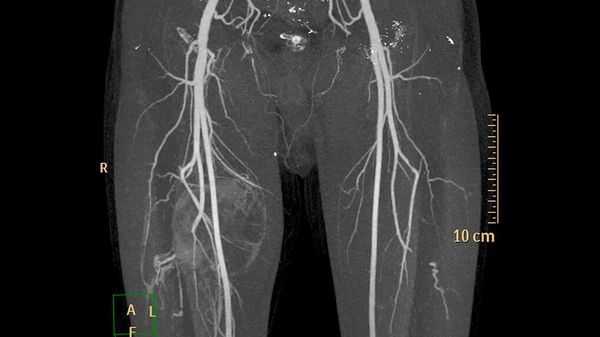

Диагностика и лечение первичных артериовенозных мальформаций нижней и верхней челюсти изучены мало, что обусловлено редкой встречаемостью патологии. Следует различать первичные и вторичные поражения челюстных костей сосудистыми мальформациями. Чтобы установить окончательный диагноз, определить сегмент поражения, источник кровотечения, характер местных гемодинамических нарушений, особенности строения аномальных сосудов, скорость и интенсивность кровотока в них, нужно провести ряд специальных и междисциплинарных диагностических исследований. Материал и методы. Представлен опыт лечения 12 пациентов с первичными артериовенозными мальформациями нижней и верхней челюсти с 2007 по 2017 г. Алгоритм обследования включает рентгенографию, компьютерную томографию, мультиспиральную компьютерную томографическую ангиографию, дигитальную субтракционную ангиографию. При предоперационной подготовке проводилась эмболизация афферентных сосудов и сосудистых полостей с использованием Onyx 18 и Гистоакрила. В зависимости от локализации и размера артериовенозных мальформаций определялась тактика хирургического лечения, объем резекции костной ткани. Для реабилитации пациентов, восстановления формы и размера челюстей, функции жевания осуществлялись костная пластика, дистракционный остеогенез, дентальная имплантация, несъемное и съемное протезирование. Результаты. Применение современных эмболизирующих материалов дает выраженный гемостатический эффект, уменьшает кровотечение во время операции. В результате лечения прекращаются кровотечения и рост артериовенозных мальформаций. Большинству пациентов с послеоперационными дефектами нижней челюсти и зубных рядов были проведены неоднократные реконструктивно-восстановительные операции. Выводы. Алгоритм обследования пациентов с первичными артериовенозными мальформациями челюстей должен включать ортопантомографию, компьютерную томографию, мультиспиральную компьютерную томографическую ангиографию и дигитальную субтракционную ангиографию. Хирургическое лечение заключается в резекции пораженного фрагмента челюсти. Целесообразно проводить органосохраняющие операции с возможной реплантацией резецированного фрагмента челюсти. Сочетание хирургического лечения и предоперационной эмболизации снижает риск возникновения массивного кровотечения во время операции.

Чтобы установить окончательный диагноз, определить сегмент поражения, источник кровотечения, характер местных гемодинамических нарушений, особенности строения аномальных сосудов, скорость и интенсивность кровотока, нужно провести ряд специальных и междисциплинарных диагностических исследований. К специальным методам относятся: рентгенологический, ультразвуковое исследование, компьютерная томография (КТ), магнитно-резонансная томография (МРТ). При К.Т. и МРТ целесообразно использовать методики КТ- и МРТ-ангиографии [5, 6]. Особенно показательна мультиспиральная компьютерная томографическая ангиография (МСКТ АГ). К междисциплинарным методам исследования относится дигитальная субтракционная цифровая ангиография (ДСА), которая проводится стационарно в специализированных отделениях [7].

Алгоритм обследования пациентов включал клинический метод обследования (сбор жалоб и анамнеза, осмотр, пальпация со стороны полости рта и наружных кожных покровов), проведение ортопантомографии, КТ, МСКТ А.Г. Всем пациентам проведена ДСА, которая в 9 случаях сочеталась с эмболизацией внутрикостных сосудистых полостей и основных афферентных сосудов из системы наружной сонной артерии. ДСА, в том числе с эмболизацией, проводилась с правой и левой стороны в зависимости от локализации АВМ и особенностей ее кровоснабжения. В качестве эмболизирующих агентов применялся препарат ONYX-18 (биосовместимый полимер, состоящий из смеси этиленвинилового спирта и диметилсульфоксида, ev3, США) у 6 пациентов и препарат Гистоакрил (2-изобутилцианметакрилат, Германия) у 3 больных [8, 9]. У 3 пациентов эмболизация не была проведена: у 1 пациентки в анамнезе с целью остановки кровотечения была перевязана наружная сонная артерия на стороне поражения и у 2 пациентов размер АВМ в области тела нижней челюсти позволял провести блоковую резекцию с предварительным внутрикостным введением Гистоакрила.